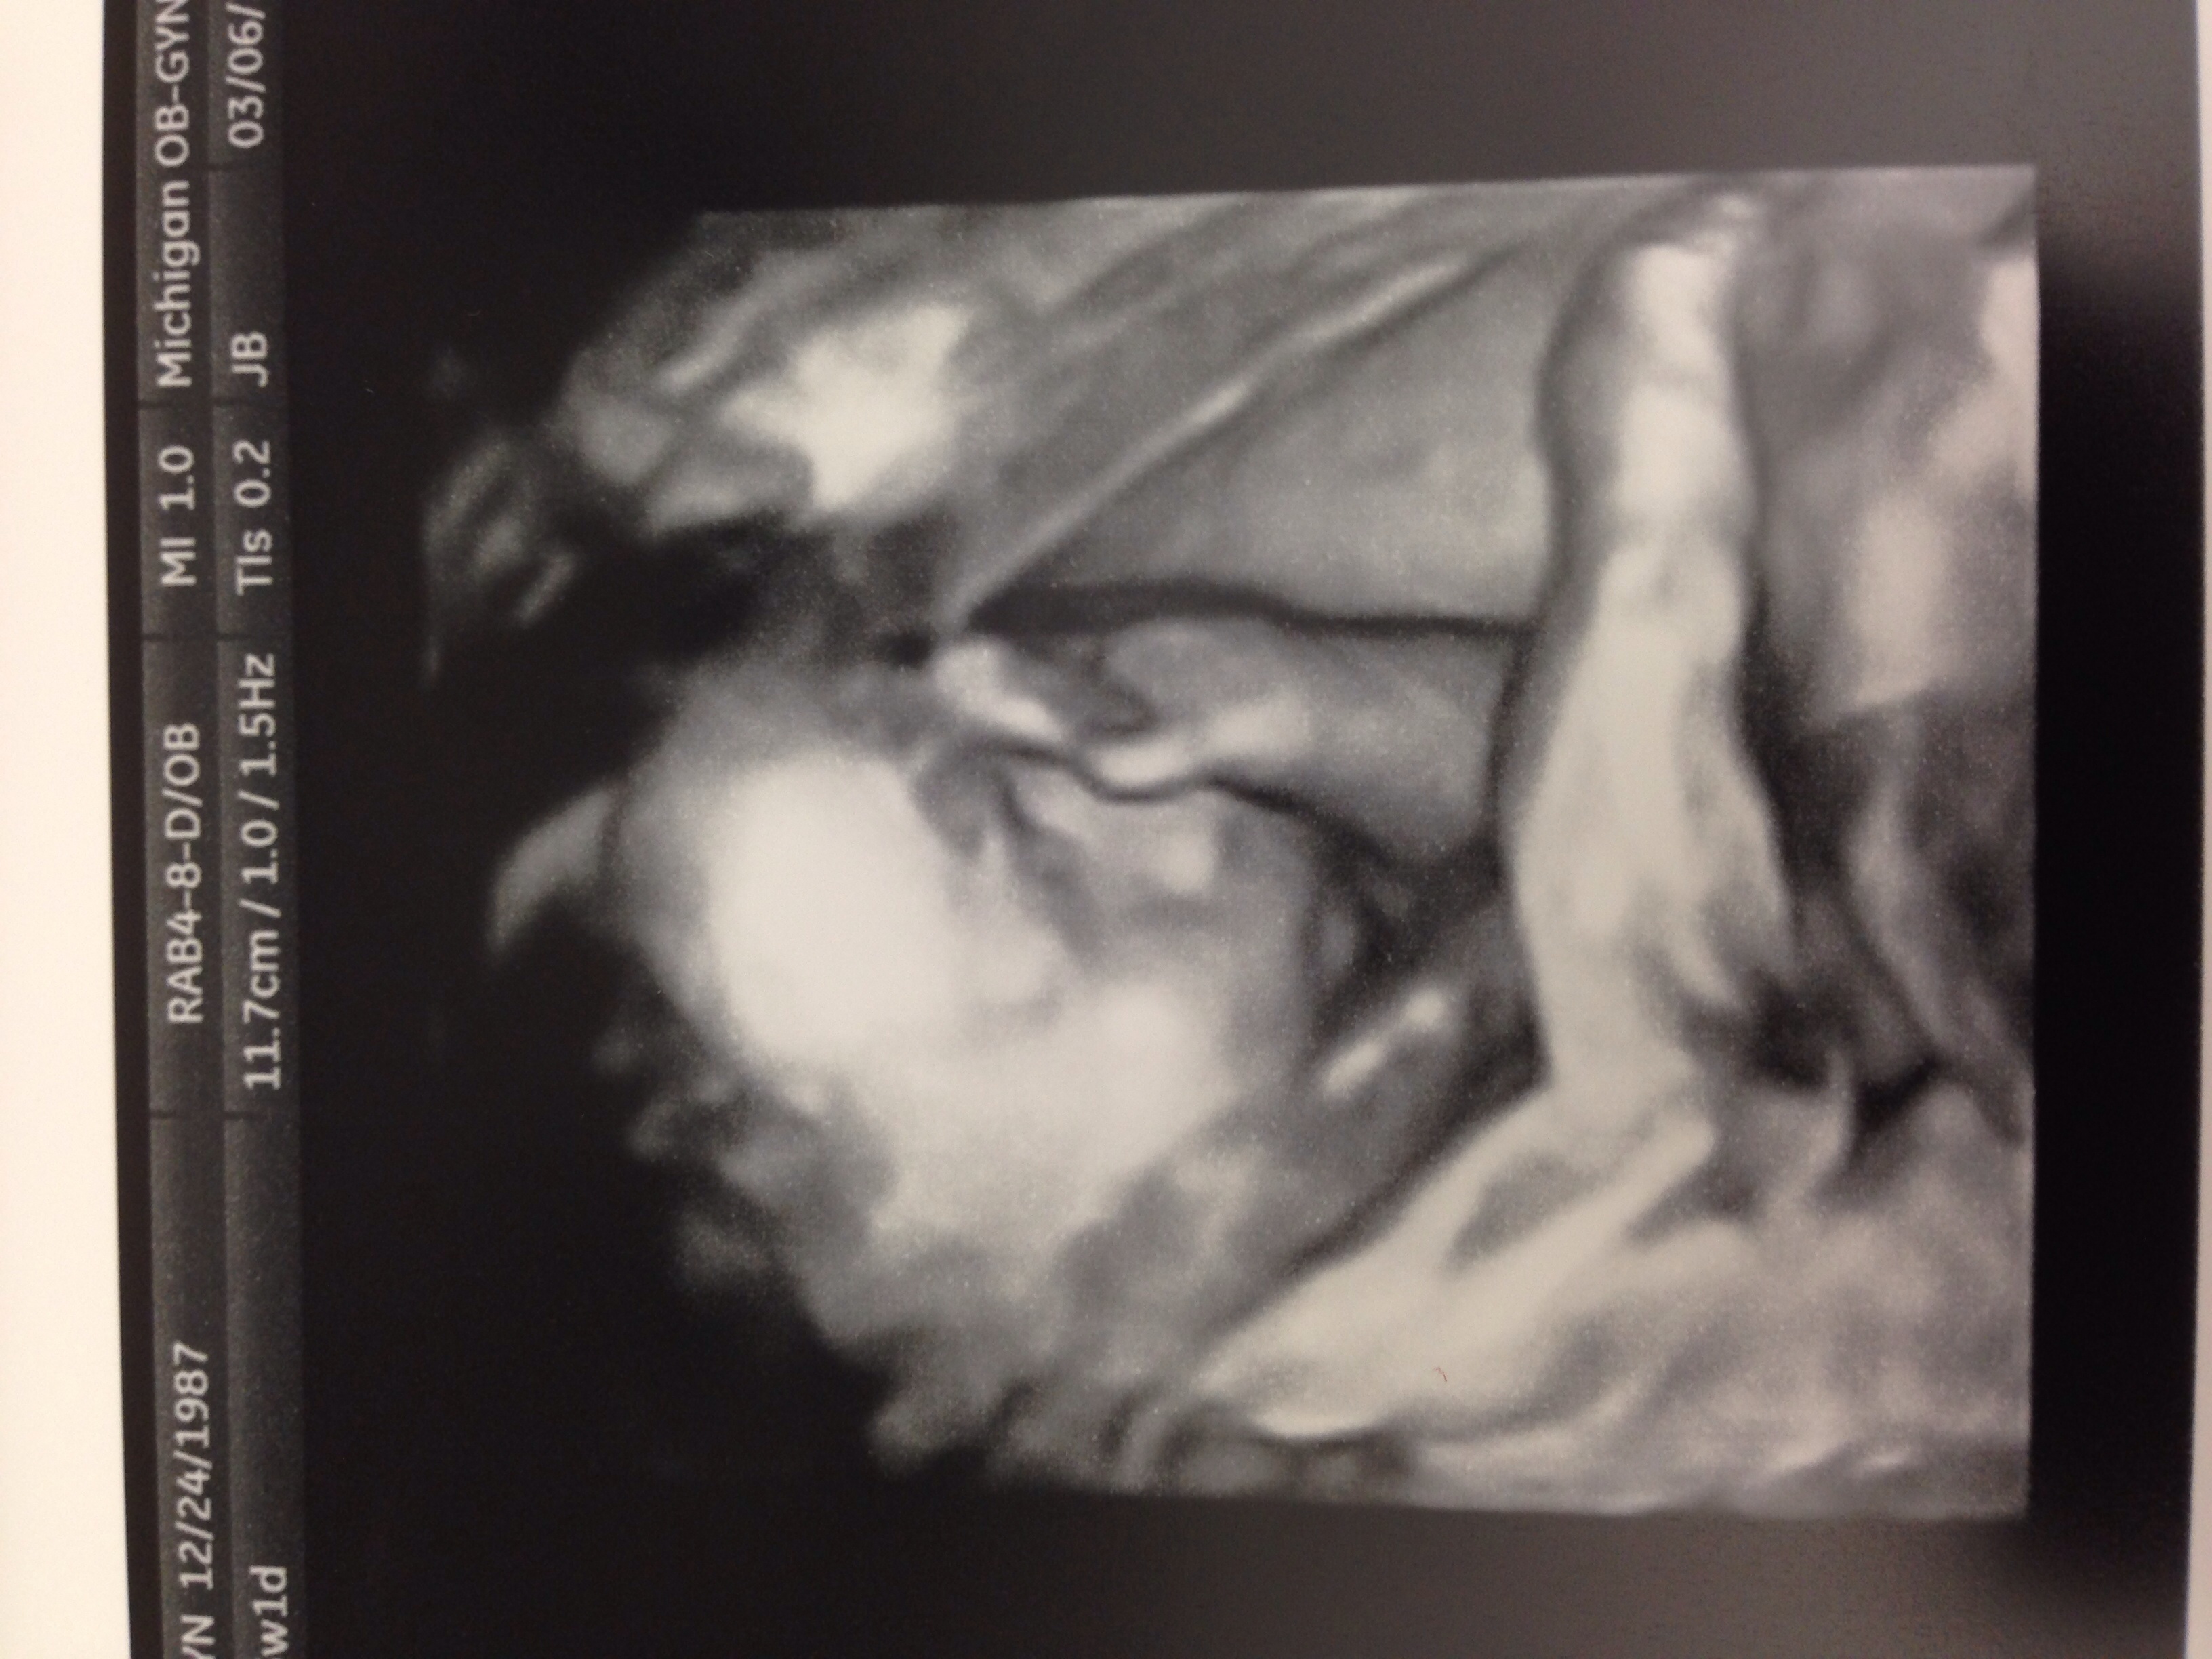

Had my 25 week check up and u/s due to my husbands heart defect and couldn't see the heart well enough last time. So far everything looks good but still can get good pics of the heart because baby is on his stomach. Oh well just means another u/s in a few weeks. Along with my glucose screen. Here's a pic of my little guy